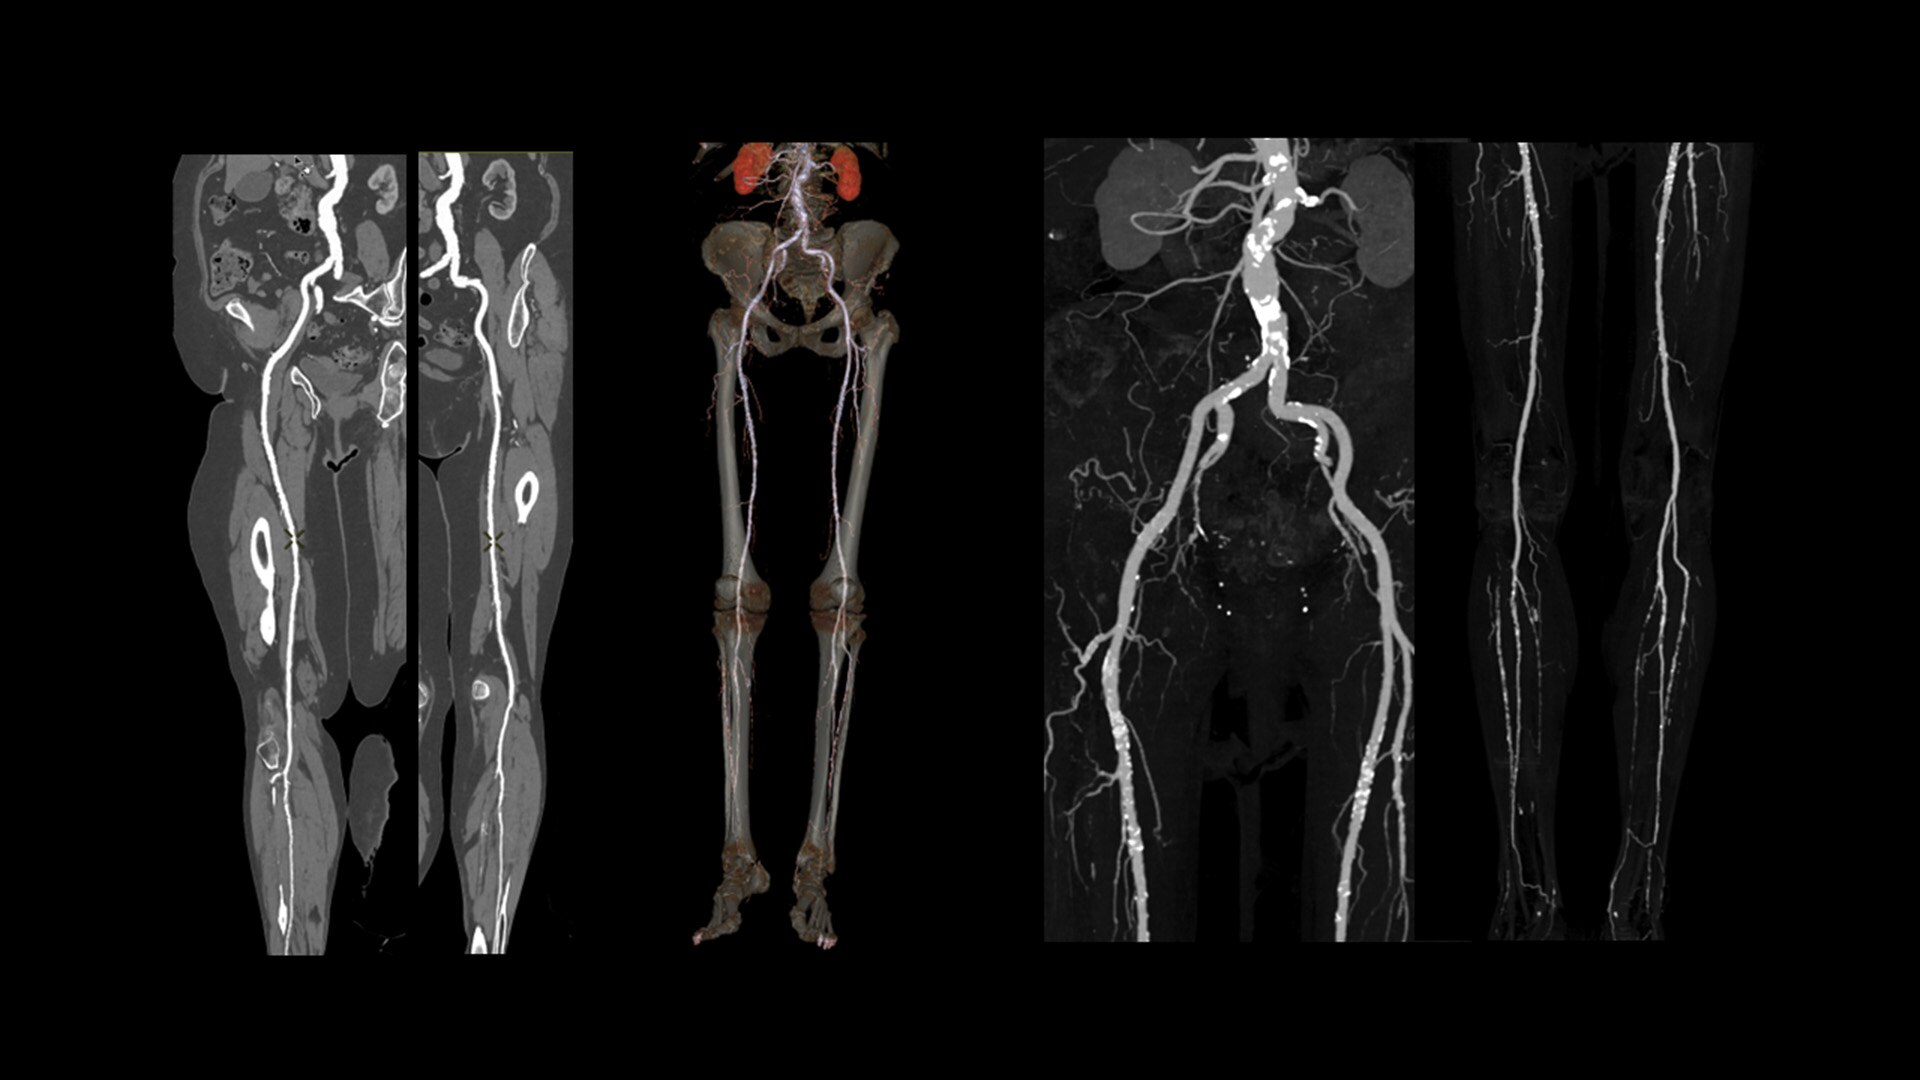

Cardiac CT has become a front-line, non-invasive imaging tool for diagnosing, treatment planning and monitoring of cardiovascular disease

Healthcare providers are striving to improve patient health but are struggling with increasingly complex exams, insufficient or inexperienced staff, and operational and capital efficiency. Revolution™ Vibe, designed to deliver leading-edge technology, features advanced cardiovascular capability. It improves patient access and operational efficiency, prioritizes patient care and supports your facility's growth with lower lifecycle costs.

Consistent, exceptional image quality for every patient

Unlimited 1-Beat Cardiac is designed to provide consistent, high-quality imaging for accurate diagnoses, even in challenging patients with atrial fibrillation, breath-holding difficulties, heavily calcified coronaries, in-stent restenosis, and situations where an ECG trace is unavailable.